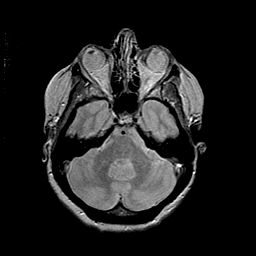

MR Study #2 -- Slice #16